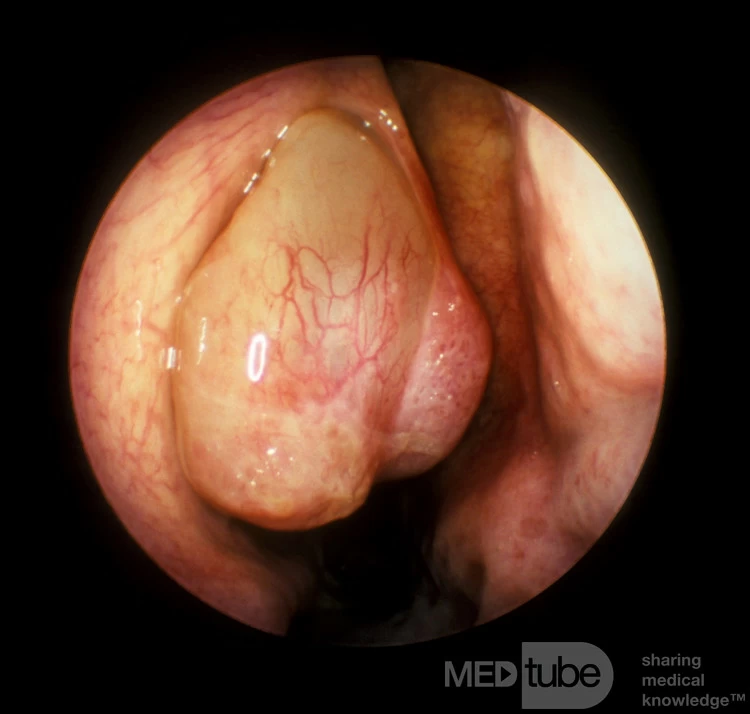

Polyp lớn này kéo dài về phía trước ra khỏi lỗ thông giữa bên phải đã đẩy cuốn mũi giữa vào trong. Polyp đã làm mỏng cuốn mũi giữa, rõ ràng là do áp lực liên tục lên vách ngăn mũi. Polyp này bắt nguồn từ phần gốc rộng từ bờ tự do của một mỏm móc lệch về trong. Không phát hiện thấy bất kỳ bệnh lý nào khác ở toàn bộ xương sàng trong quá trình tìm kiếm. Được cung cấp bởi Giáo sư Heinz Stammberger, Đại học Graz, Áo.